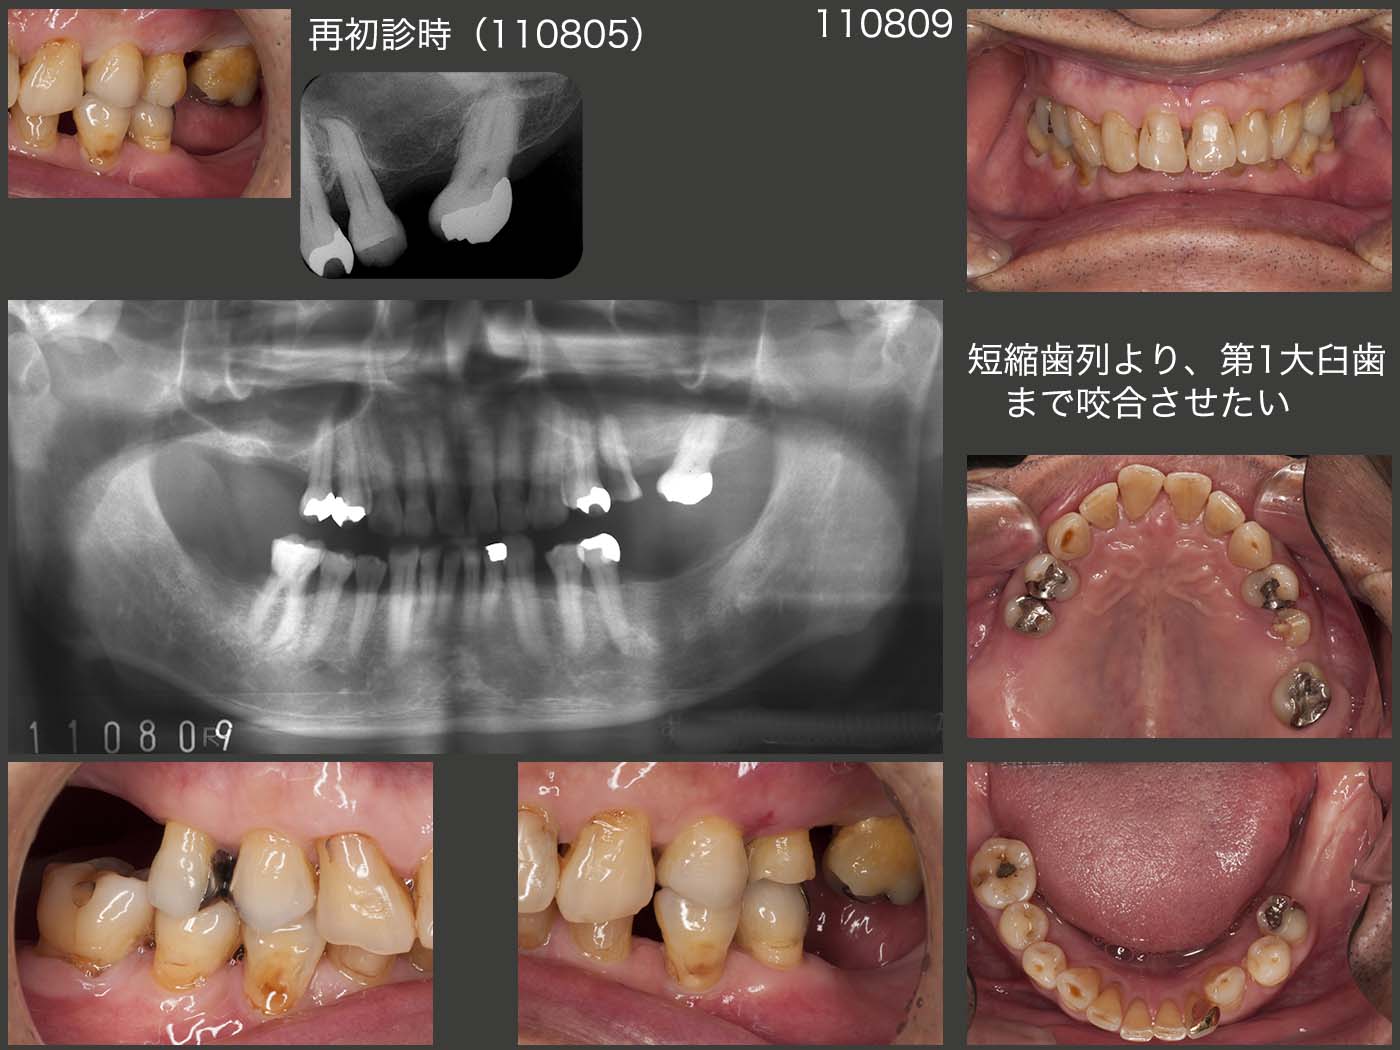

1993年初診,54歳男性.今回は2011年8月,左上5の痛みで来院.デンタルX線写真からは特に異常はみられないが,口腔内をよく観察すると,歯冠が破折し,破折線が歯髄まで達していた.

06年に右上6を歯周病で抜歯した後は,11年まで大臼歯部の咬合が失われた状態であった.そのため小臼歯部で咀嚼するしかなく,長年にわたる加重負担により歯冠破折が生じたと想像できる.もし,左上5が無髄歯なら,歯根破折が生じ,抜歯となっていたであろう.